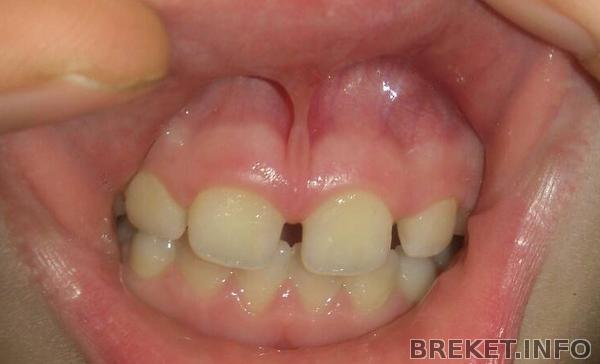

Здравствуйте, мы пришли к ортодонту с вопросом подрезать ли дочке уздечку верхней губы, чтоб убрать диастему, между верхними резцами (по направлению терапевта). Но врач сказал что его наша уздечка совсем не беспокоит, он видит проблему в прикусе, а конкретно в том что нижние зубы сильно высоко заходят за верхние. Им предложено было лечение: изготовление пластинки которая не даст смыкаться жевательным зубам и они через пол года подтянутся вверх и исправят низкий прикус (он его так назвал) Еще дополнительно пластинка сдвинет в кучу 4 верхние резца и изменит их наклон немного вовнутрь (Зачем? Зубы действительно не туда смотрят?).

Верхние зубы и так уже в наклоне (см.фото) Куда еще то? Глубокий прикус усугубить?